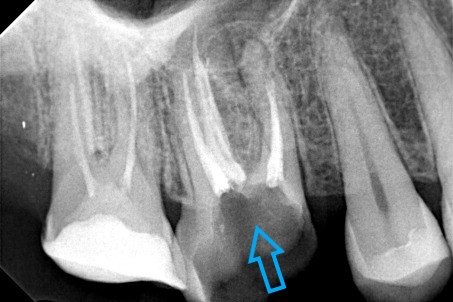

Επανάληψη απονεύρωσης σε τρία άνω πρόσθια δόντια